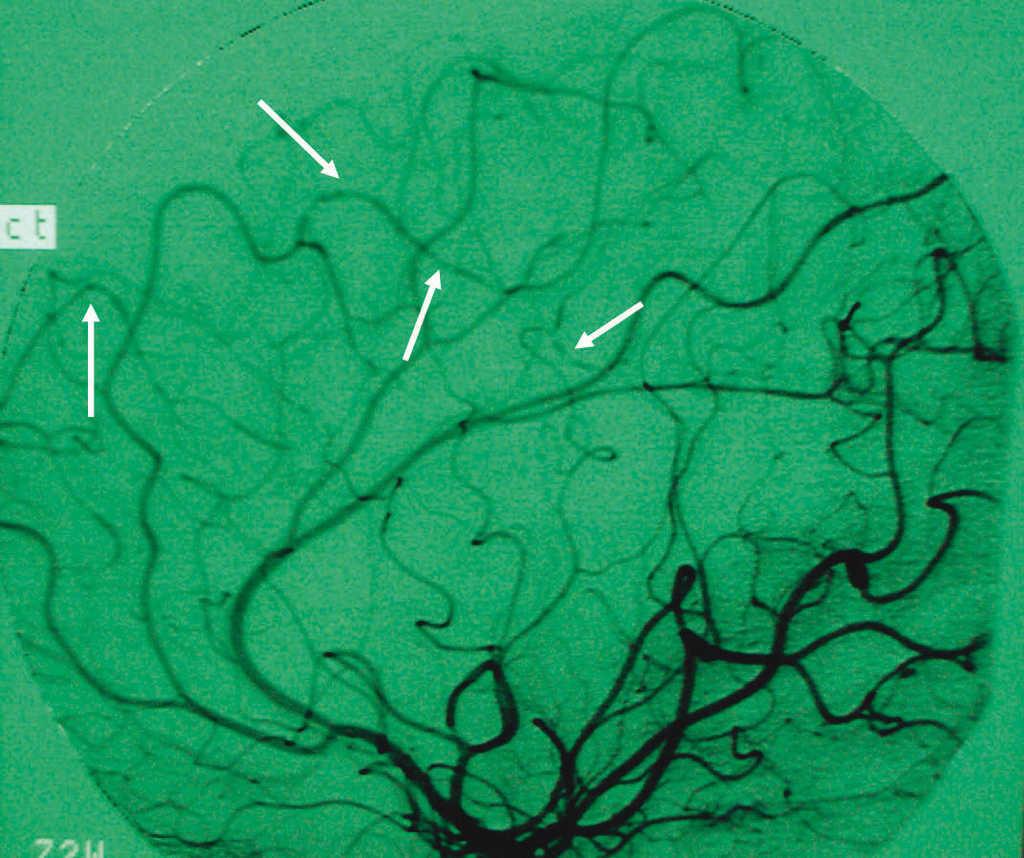

Se trata de una paciente de 14 años con deposiciones mucosanguinolentas de 15 días de evolución y pérdida de 8 kg en el último mes. Analíticamente presenta anemia microcítica, hipoproteinemia, hipoalbuminemia, trombocitosis y marcadores inflamatorios elevados. Los estudios microbiológicos en heces son negativos. A las 24 h del ingreso, coincidiendo con pico febril, presenta disminución brusca de fuerza en hemicuerpo derecho, ataxia y afasia. La TC cerebral muestra lesión hipodensa yuxtacortical en convexidad parietal izquierda sugestiva de lesión isquémica o absceso cerebral, por lo que, ante la duda diagnóstica, se instaura corticoterapia antiedema cerebral y antibioterapia de amplio espectro. La rectoscopia muestra hallazgos sugestivos de proctitis ulcerosa con biopsias compatibles. Tras iniciar el tratamiento anteriormente descrito desaparece la fiebre y mejora la clínica neurológica. Paralelamente presenta mejoría progresiva de la sintomatología digestiva. Para descartar trombosis del seno venoso, se realiza estudio de hipercoagulabilidad (factores V, VII, VIII y X de coagulación, antitrombina III, mutaciones de protrombina, proteínas C y S, homocisteína, anticoagulante lúpico, funcionalismo plaquetario, y anticuerpos anticardiolipina) siendo normal. Dada la mejoría, es dada de alta con corticoides en descenso y mesalazina. Una semana después reingresa por empeoramiento de su clínica digestiva. La colonoscopia realizada es compatible con pancolitis ulcerosa. Al no responder a corticoterapia intravenosa se añade ciclosporina A, lográndose así controlar la situación. La angiorresonancia cerebral realizada muestra disminución de la imagen patológica previa. Dos meses tras el alta y en tratamiento de mantenimiento con azatioprina, presenta crisis convulsiva tónico-clónica generalizada. Una nueva TC cerebral muestra lesiones residuales parietales y nuevas lesiones bilaterales afectando convexidades parietales, sugestivas de infartos. Se solicita arteriografía cerebral que muestra vasculitis de ramas distales de arterias cerebrales anterior y media (fig. 1). Se instaura tratamiento con pulsos mensuales de ciclofosfamida y esteroides orales en dosis decrecientes, asociados a azatioprina, tratamiento anticonvulsivante y profilaxis con heparina y AAS, presentando buena evolución neurológica. Tres meses después reinicia clínica digestiva que no responde a corticoterapia intravenosa, decidiéndose colectomía total e ileostomía. Presenta evolución posquirúrgica satisfactoria, lo que permite la supresión progresiva de su medicación. Una nueva arteriografía 7 meses tras la intervención, muestra desaparición de las imágenes vasculíticas. Actualmente realiza profilaxis con AAS mientras que sangrados esporádicos por el muñón rectal, en espera de la creación del reservorio, se han controlado con mesalazina tópica.

Figura 1. Arteriografía cerebral de la paciente en la que se observan tortuosidades (flechas) sugestivas de vasculitis en las ramas distales de las arterias cerebrales anterior y media.